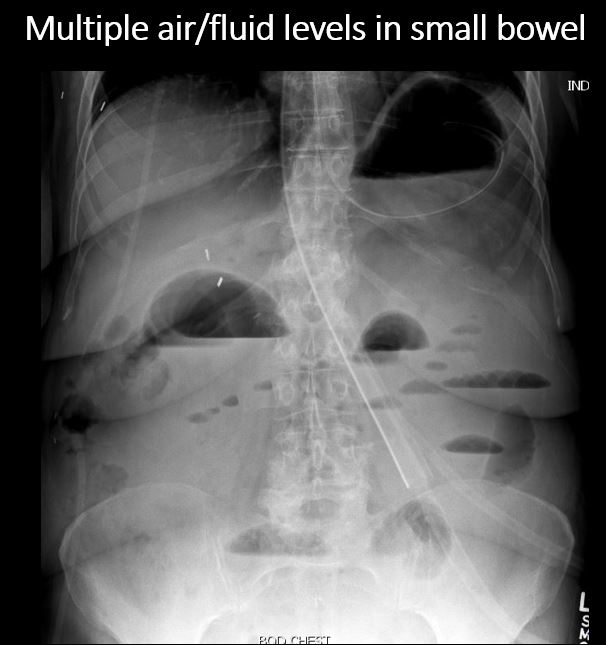

There is dilatation with gas or fluid of multiple or diffuse loops of small bowel greater than 3 cm, or a few local loops of small bowel greater than 3cm. [Yes/No]

There are more than 3 air/fluid levels or “string of pearls (beads) sign” involving the small bowel. [Yes/No]